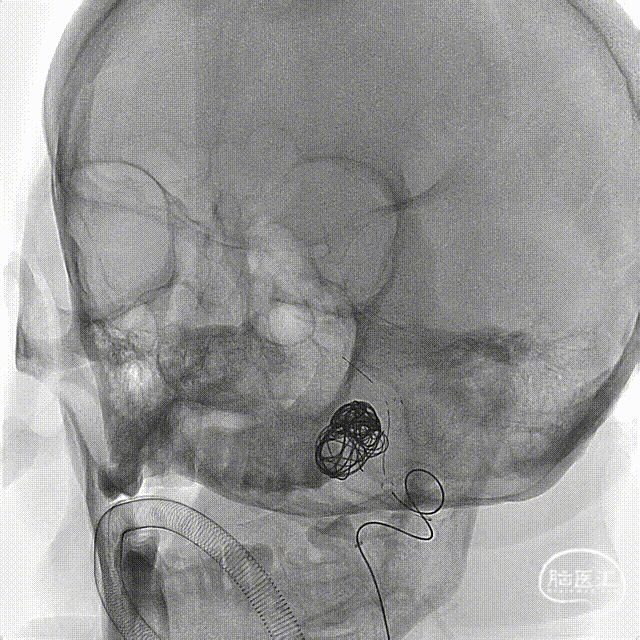

建立治疗通路后,在微导丝引导下到位塑形好的支架微导管至基底动脉上段;微导丝导引下上高塑形好的弹簧圈微导管至动脉瘤内;完成后续支架辅助弹簧圈栓塞;在整个过程中加奇生物Tethys®中间导引导管提供稳定支撑。

左右滑动切换图片

术后造影提示动脉瘤内弹簧圈致密填塞,瘤颈封堵可,载瘤动脉、基底动脉、双侧大脑后动脉通畅。